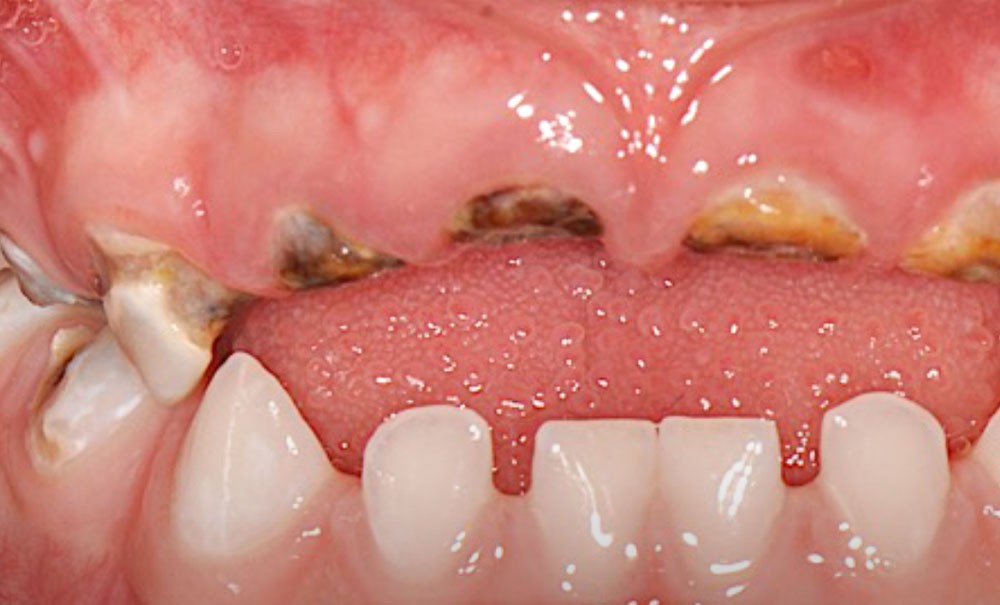

L’OMS recommande un allaitement exclusif jusqu’à l’âge de 6 mois, et associé à d’autres aliments jusqu’à 24 mois [3]. S’il n’est plus nécessaire de démontrer les bienfaits de l’allaitement sur la santé globale de l’enfant, il reste néanmoins utile d’en prévenir certaines pratiques parfois inadaptées pouvant conduire à l’apparition de carie de la petite enfance (CPE) (fig. 1 et 2). L’allaitement au sein exclusif pendant une période de 6 mois présente bien des avantages pour le nourrisson et la mère, et notamment celui de protéger contre les infections gastro-intestinales, aussi bien dans les pays en développement que dans les pays industrialisés. Par ailleurs, une mise au sein précoce, dans l’heure qui suit la naissance, réduit le taux de mortalité.

Les études soulignent également les bienfaits de l’allaitement sur la santé orale : il favorise notamment le développement de la musculature, la croissance maxillo-faciale et limite les malocclusions chez l’enfant [4]. Si la cariogénicité du lait maternel n’a pas été examinée de manière approfondie, des études suggèrent qu’elle est plus importante que celle du lait de vache, mais moins importante que celle des préparations infantiles. Ceci est à considérer notamment lors de consommations fréquentes [5, 6]. Par conséquent, il a été mis en évidence que l’allaitement maternel pourrait être un facteur de protection contre la CPE jusqu’à l’âge de 12 mois. Pour autant, des pratiques d’allaitement à la demande, après l’éruption des dents temporaires, et notamment la nuit, associées à des pratiques de cosleeping (ou co-dodo : l’enfant dort avec la mère), contribueraient à développer la CPE après 12 mois [7, 8]. Si d’autres facteurs sont également à considérer dans le développement de la CPE [9], les études soulignent que l’allaitement prolongé [au-delà de 24 mois]…